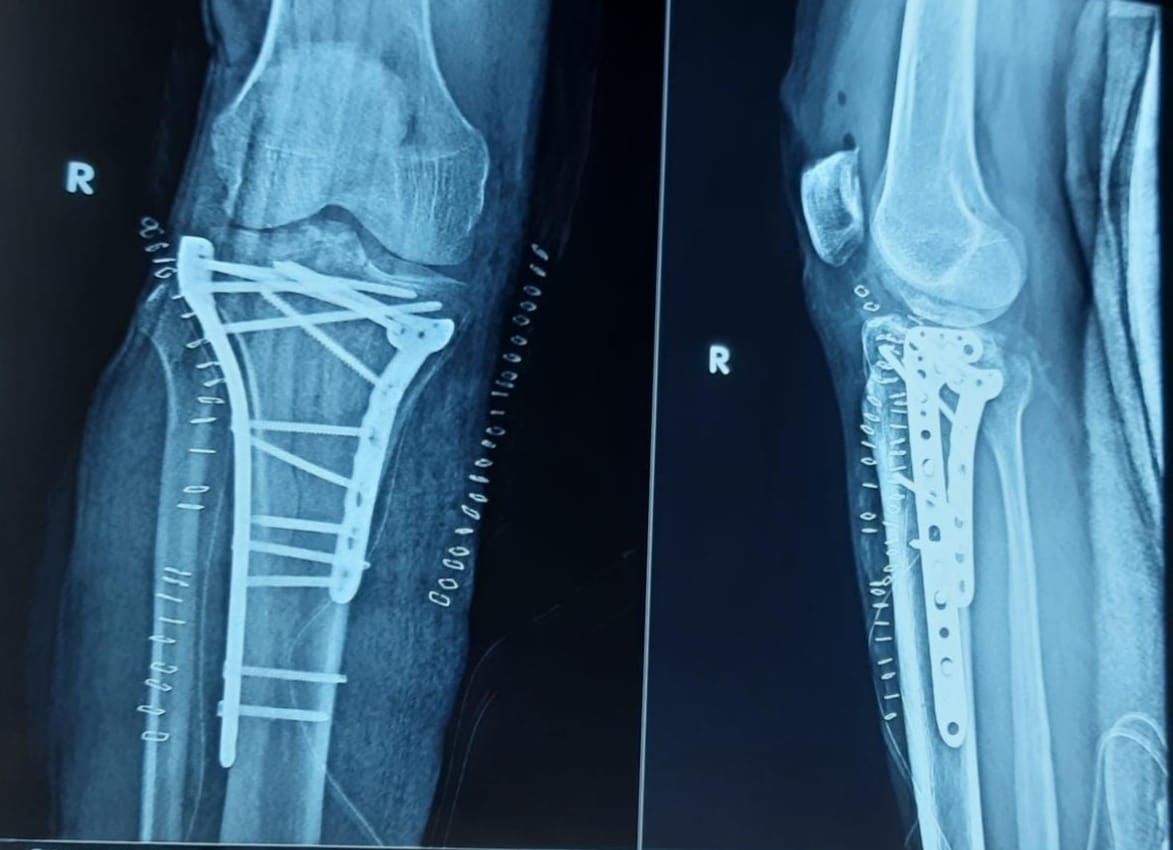

TREATMENT FOR FRACTURES OF LONG BONES